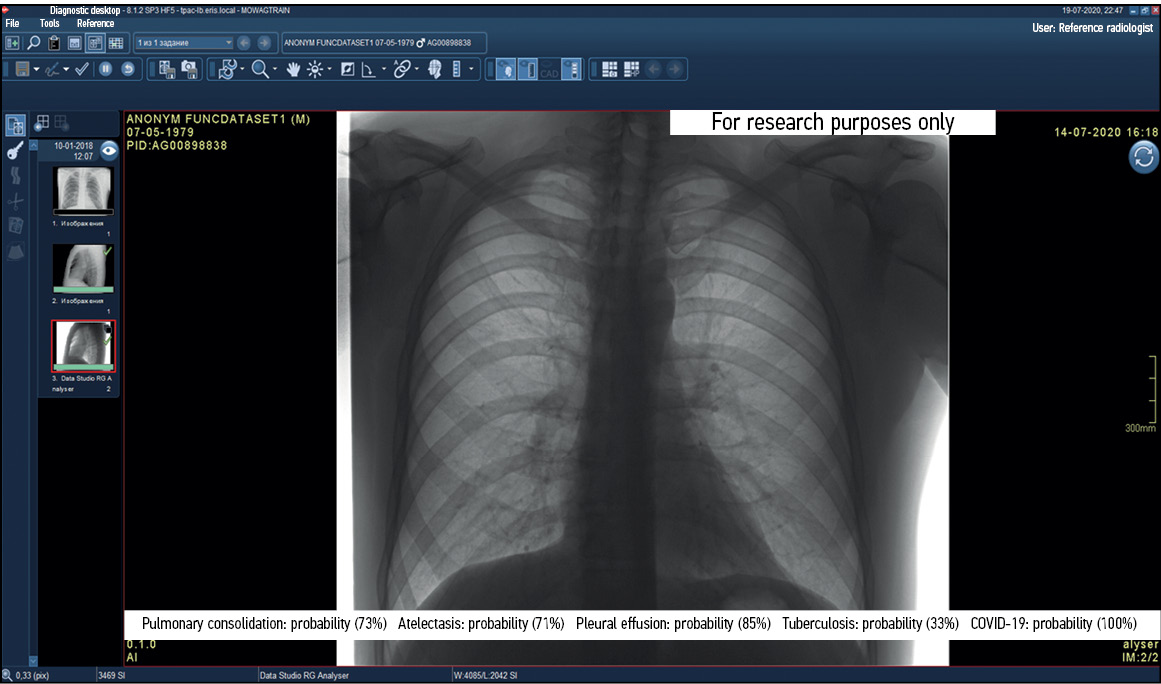

Functional testing is a stage wherein software functions specified by a supplier are checked for availability and functionality. This testing is performed at the technical and clinical levels. On a technical level, the software is assessed based on the following criteria: prioritization of research (triage), availability of an additional series of images from the software, presence of the other series’ name, presence of a graphical designation of software on the images of the different series, presence of a warning label “For research purposes only” on images and in DICOM SR, possibility of series synchronization, displaying the probability of abnormality, indication of the category of abnormality, and availability of complete DICOM SR protocol structure (Figures 2 and 3).

Fig. 2. Main components of the result of using artificial intelligence–based software with images: A reference example.

Fig. 3. Main components of the result of using artificial intelligence–based software with DICOM SR: A reference example.

This part of functional testing should be performed by technical specialists in accordance with the basic functional requirements developed by the Moscow State Budgetary Institution “Scientific and Practical Clinical Center for Diagnostics and Telemedicine Technologies of the Moscow Department of Health” (Center for Diagnostics and Telemedicine).14 The medical assessment of software functions should be performed by medical experts in accordance with basic diagnostic requirements developed by the Center for Diagnostics and Telemedicine.15 Basic diagnostic requirements include criteria, such as mandatory and optional content of software response, format, and form of the submitted response. Basic functional and diagnostic requirements contain common requirements for all software and specific requirements based on the clinical task for which the software is designed.

If critical nonconformities are identified, software testing is stopped until the supplier eliminates their causes. Inconsistencies with basic functional requirements are critical because they negatively affect the HCP work processes and, directly or indirectly, the patient’s life and health (Figures 4 and 5).